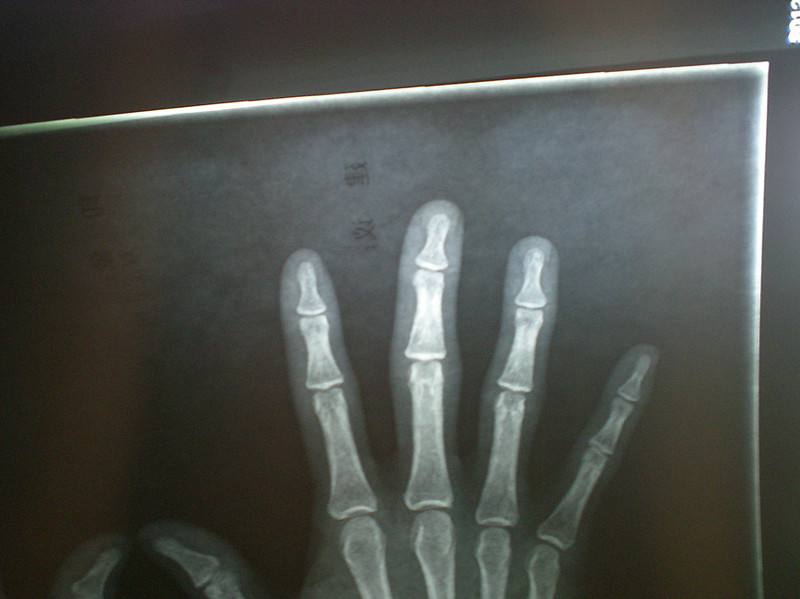

风湿痛这种疾病发生之后会侵犯人的关节,同时还会侵犯人的肌肉,骨骼,以及关节周围到一些软组织,比如说风湿痛可以侵犯患者的韧带,滑囊,筋膜等部位,这种疾病会引起患者表现出局部性的或者是全身性的疼痛,这种疾病属于麻痹症的一种类型,在中医看来,风湿热是因为风邪和湿邪导致的,发病之后患者会感觉疼痛,身体发热,睡觉出汗,小便不利,关节疼痛酸痛等现象。

综上所述,风湿痛不是一种单独的疾病,而是一些疾病而导致的后果,所以说,当患者出现风湿痛之后一定要到医院做检查,查清楚具体的原发病,然后针对疾病进行治疗。